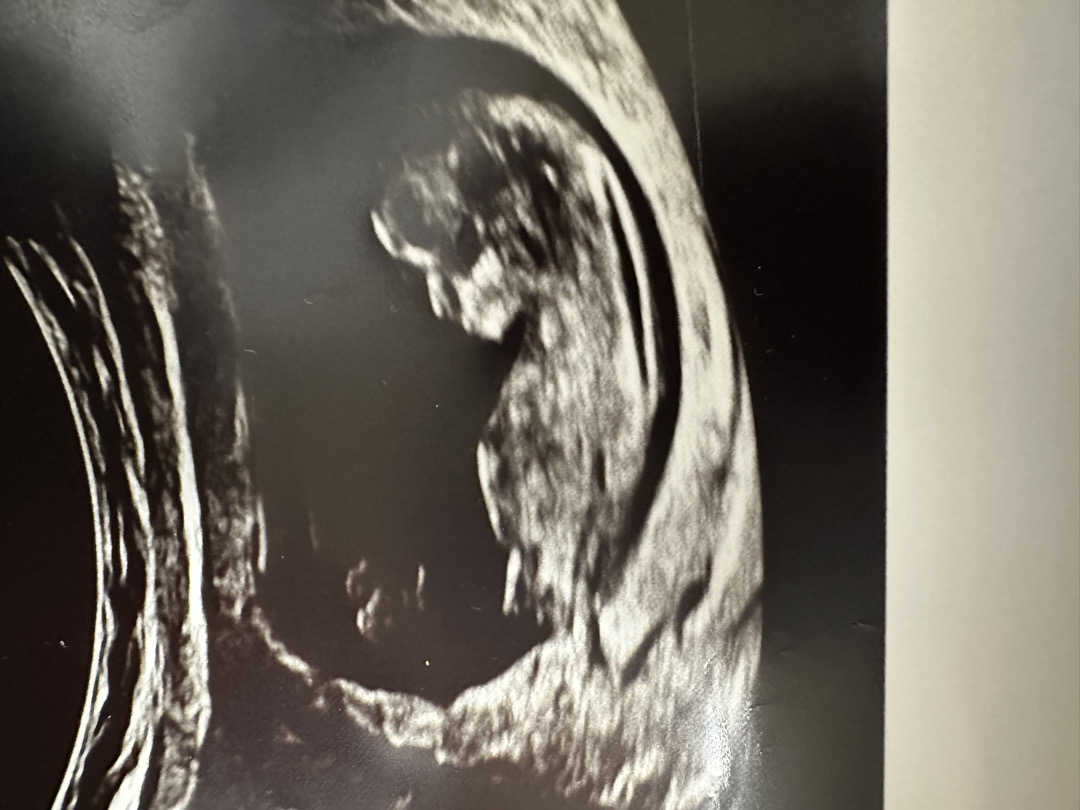

12주 각도법 봐주실분❤️

투표부탁드려요❤️ 감사합니다